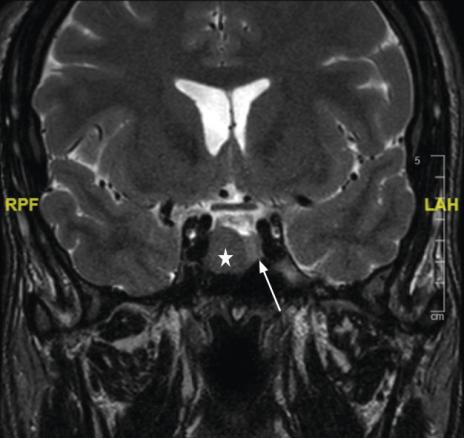

La réalisation d’une IRM hypophysaire permet de visualiser la tumeur (fig. 3, 4 et 5), d’évaluer sa taille et son éventuelle extension aux structures adjacentes.